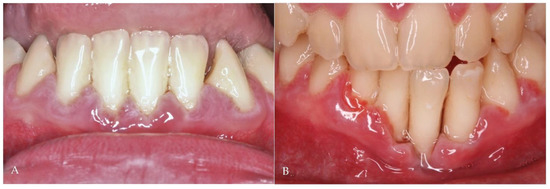

2.1. Case Report